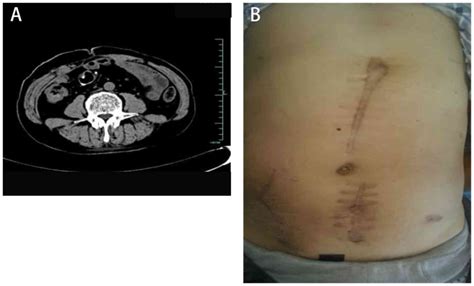

Strict adherence to the surveillance schedule set by your medical team is vital. This often includes regular colonoscopies, imaging tests (such as CT scans), and blood tests to monitor tumor markers. These screenings are designed to detect any potential issues, such as the return of polyps or cancer, at the earliest possible stage, when they are most treatable.